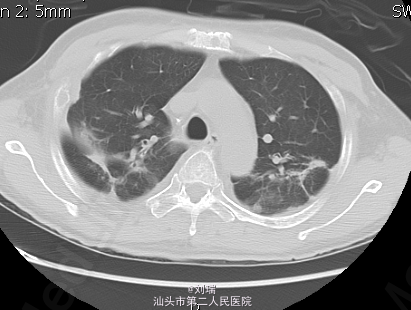

经上述处理,患者症状稍好转后行胸CT增强:双肺上叶继发型肺结核,双肺散在感染性病变;心包少量积液;双侧少量胸腔积液。经感染科会诊:考虑结核急性发作期可能性不大。继续上述对症处理后,患者症状逐渐好转;应用万珂后骨痛症状较入院时好转。 讨论:因万珂所致急性肺损伤发生率极低;最终考虑该患者为哮喘发作;化疗后出现气促、呼吸困难是否与万珂相关?